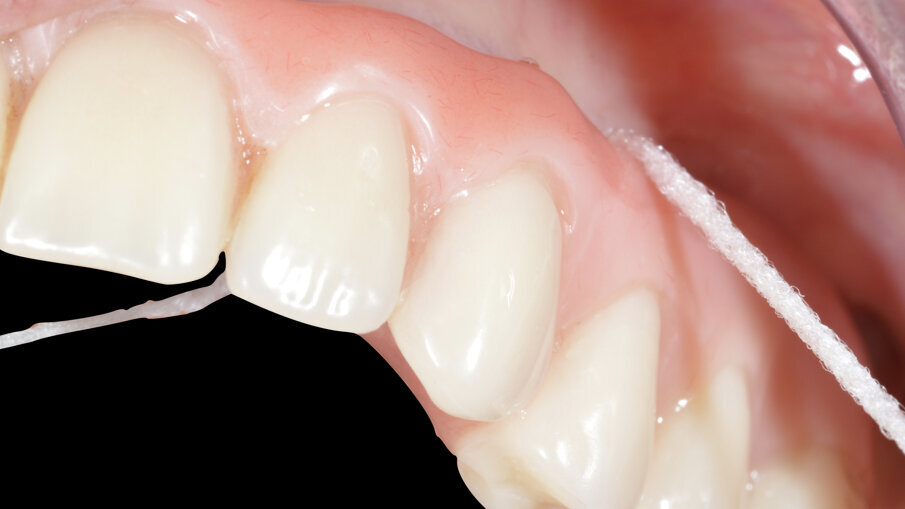

Dopo 3 mesi la situazione dell’abutment, una volta smontato l’healing abutment, è di quelle desiderabili in una protesi su impianti (Fig. 15). Terminato il lavoro con la consegna del manufatto protesico, si procede con la spiegazione, in vari appuntamenti delle manovre di igiene per il corretto mantenimento del lavoro nel tempo. Per la rimozione di placca batterica fresca si istruisce il paziente all’utilizzo di super floss per la detersione nella zona confine tra protesi e tessuti molli (Fig. 16). Super floss di oral-b è utilizzato anche per le manovre di igiene orale in studio per l’igiene dei monconi implantari.

Questo tipo di soluzione nasce dall’idea di facilitare l’inserzione del filo tra un dente e l’altro e per pulire meglio le strutture protesiche ancorate agli impianti (Fig. 17). È realizzato in materiale sintetico di un certo spessore ma morbido e adattabile a tutte le superfici. È spugnoso ed elastico allo stesso tempo e assorbe i residui di biofilm nella fase di deplaquing. L’inseritore in plastica consente un rapido inserimento del filo sia negli spazi interdentali si tra impianto e dente o fra barre e gengiva o tra protesi e mucosa vicino alle strutture protesiche. Pulisce rapidamente e in modo uniforme e consente un controllo accurato dell’igiene delle superfici trattate. Possiamo affermare che è un efficace strumento per l’igiene orale domestica.

Fig. 16_Manovre di igiene domiciliare con superfloss.

Fig. 17_Manovre di igiene professionale per la pulizia degli ancoraggi implantari.